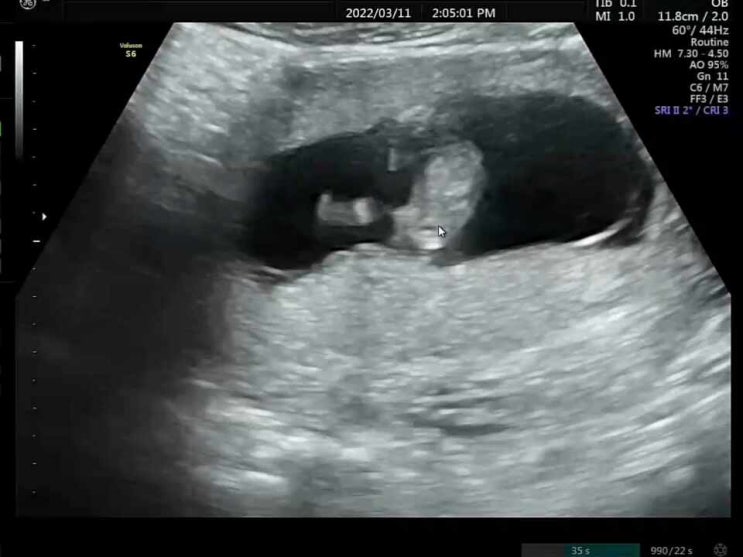

[임신30주차 그리고 조기수축 입원과 퇴원]

30주 정기검진받는날! 오전에 진료보러갔는데 울또복이가 자고있는 시간이라서 과연 초음파 잘 볼수있을지 ...